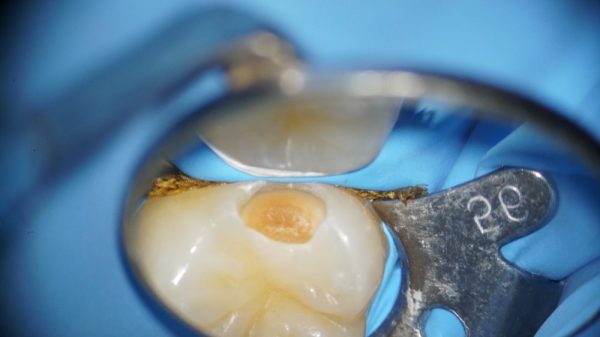

虫歯染め出し液を使用したところです。

虫歯だけを染め出して健康な部分は染まらない液です。

これによって虫歯だけを選択的に削ることができます。

健康な歯を可能な限り削らない歯を長持ちする治療が可能になります。

ラバーダムマスクをして唾液の侵入や舌、頬を排除し、湿度をコントロールします。

詰め物の治療は濡れたらくっつきません。しかし、お口の中は唾液や湿度で接着するのにとても都合が悪いです。そこでラバーダムシートという歯だけを露出させて治療することで高い接着力を可能にします。